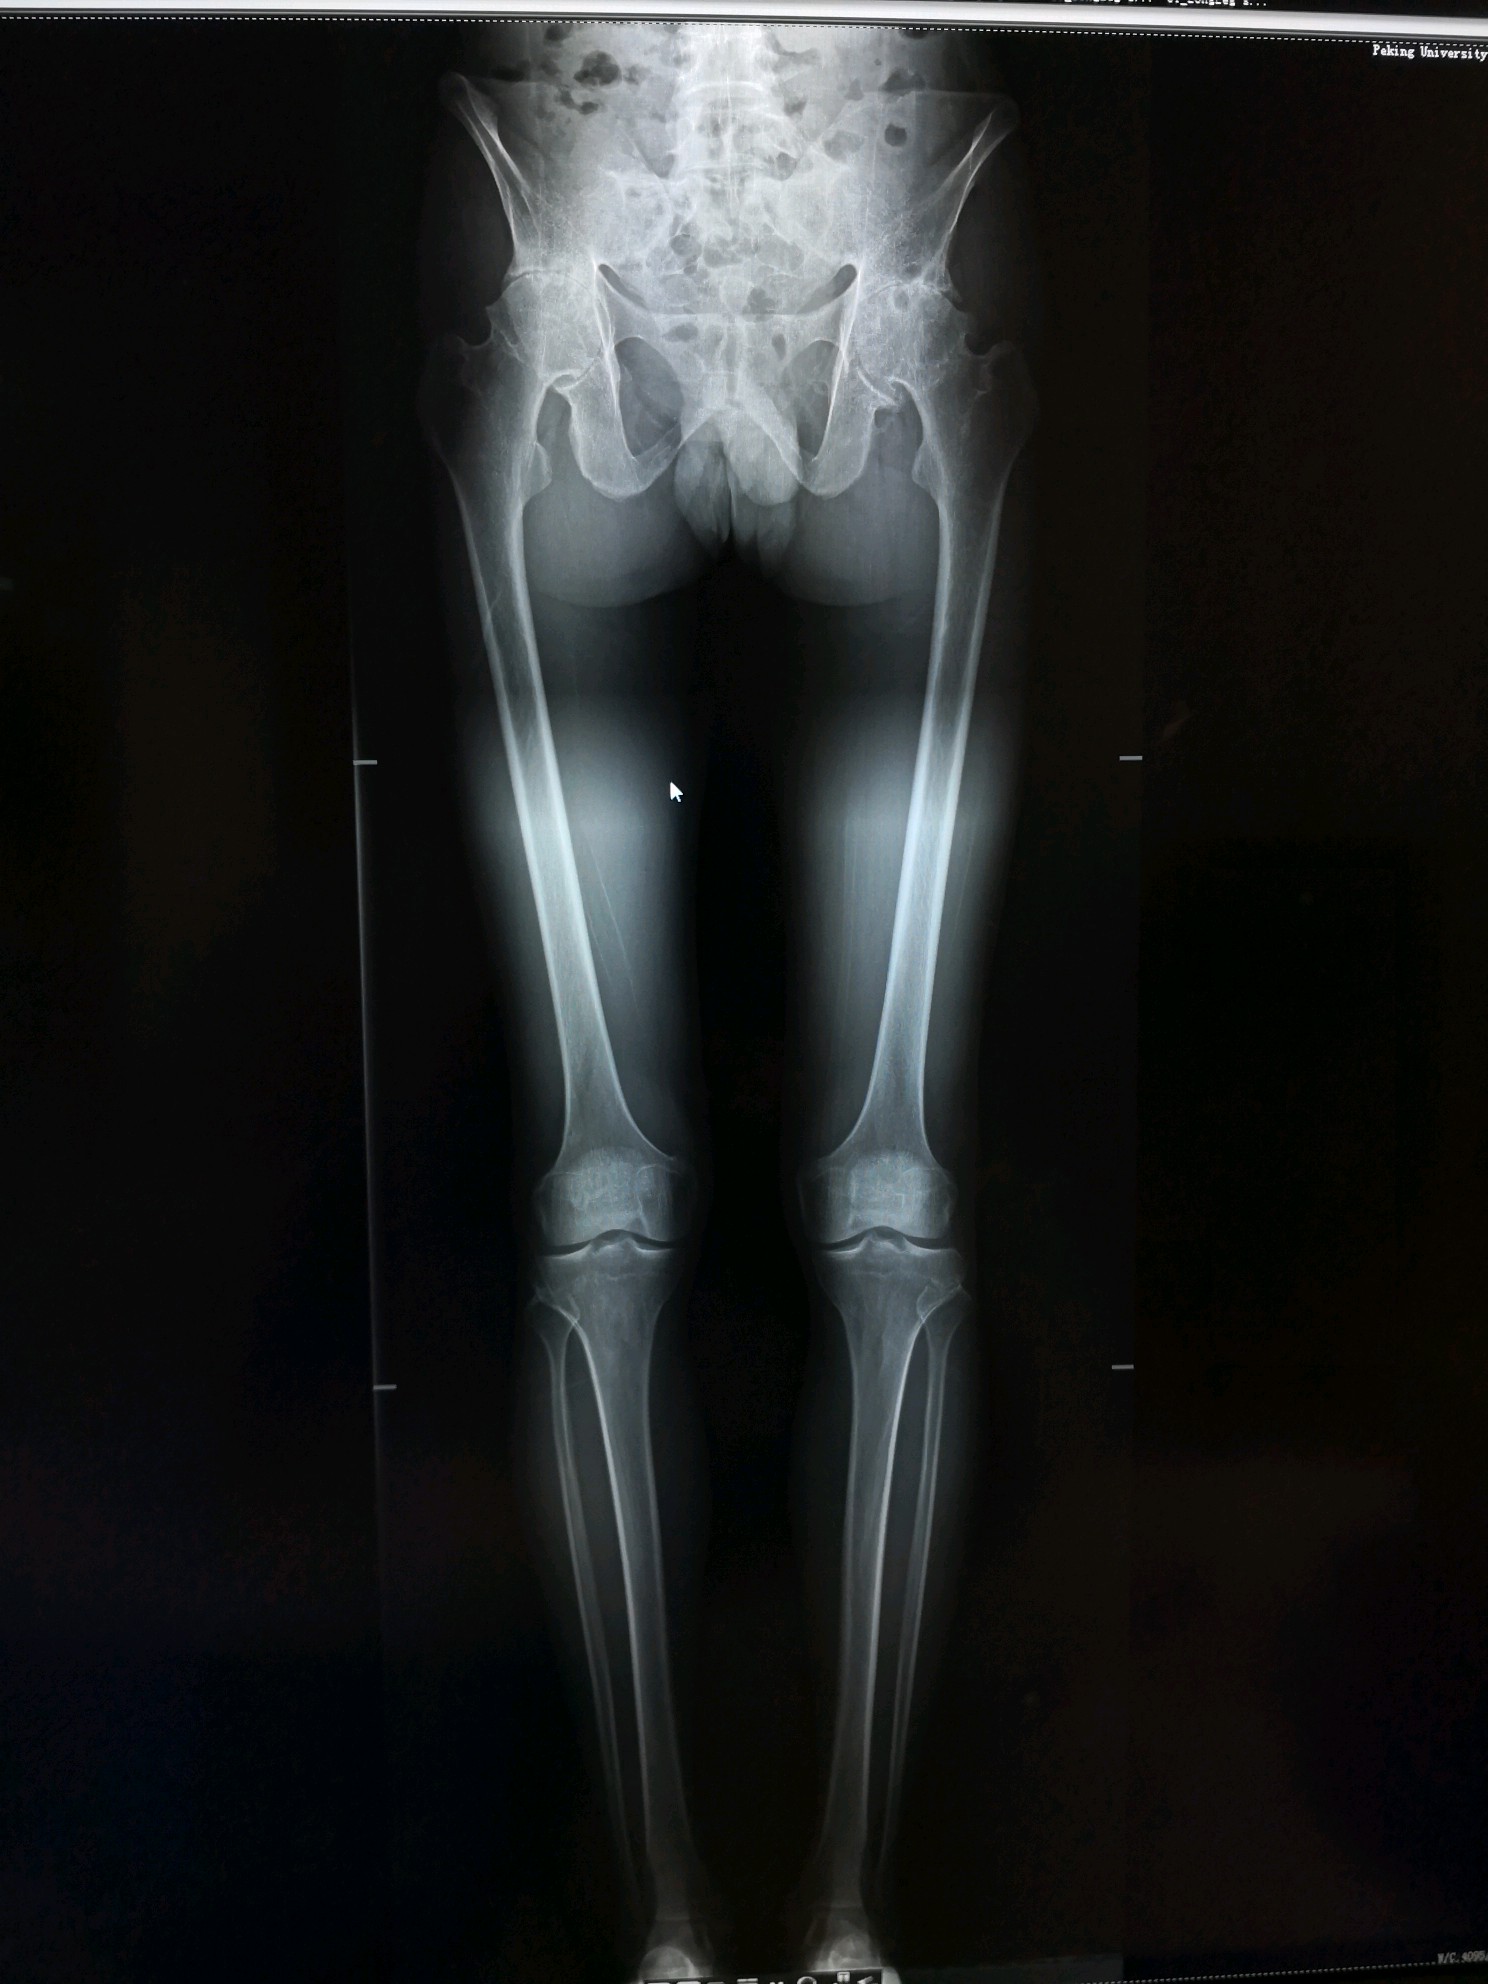

术前双下肢全长片

图片发自160医生App